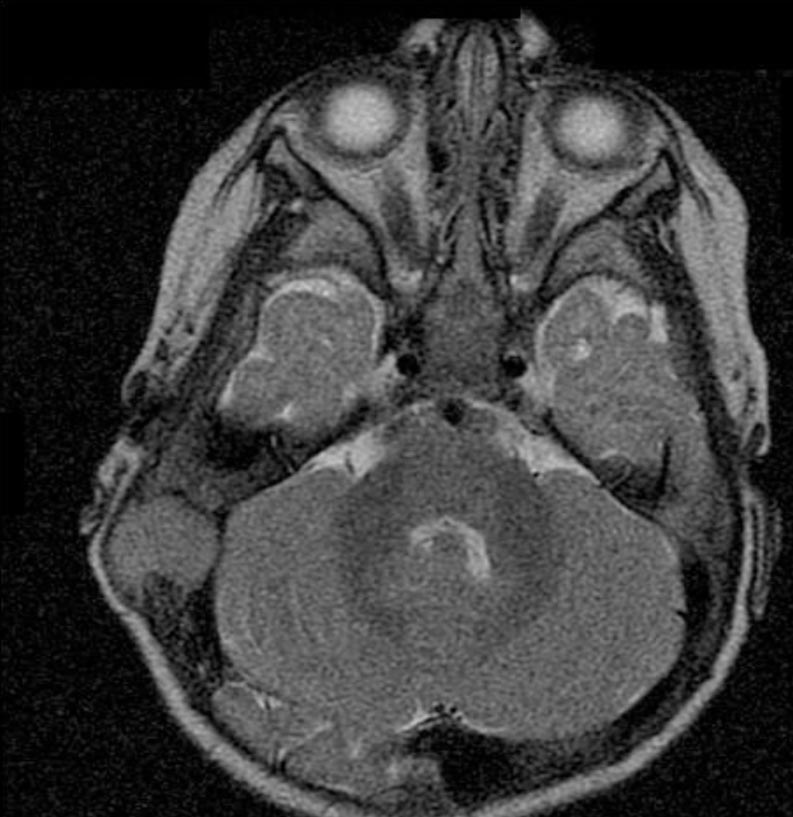

A questo punto viene eseguita una Risonanza Magnetica Nucleare (RMN) per definire l'eventuale coinvolgimento dell'encefalo: si documenta una lesione che determina un'ampia osteolisi a tutto spessore della teca cranica, giungendo a contatto con il cervelletto (Figura 1 e Figura 2). La Tomografia Computerizzata (TC) conferma il reperto (Figura 3).

Figura 2. Immagine alla RMN assiale dipendente dal T2. Il tessuto patologico, isointenso, rispetto alla sostanza grigia prende rapporti con la superficie cerebellare.